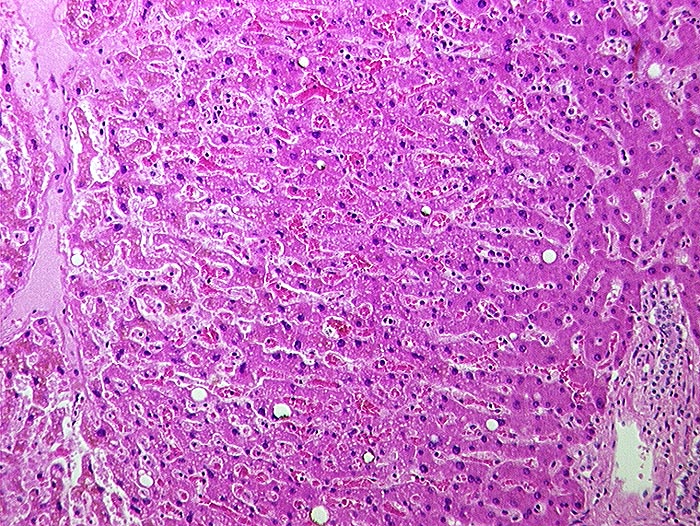

Subakute Stauung

vaskulär / Durchblutungsstörung

Leber

Links eine Zentralvene, rechts ein Portalfeld. Die Sinusoide sind vor allem um die Zentralvene erweitert und die Leberzellplatten leicht verschmälert (Druckatrophie).

In der Bindegewebsfärbung kein vermehrter Fasernachweis rund um die Zentralvene.

Histologie